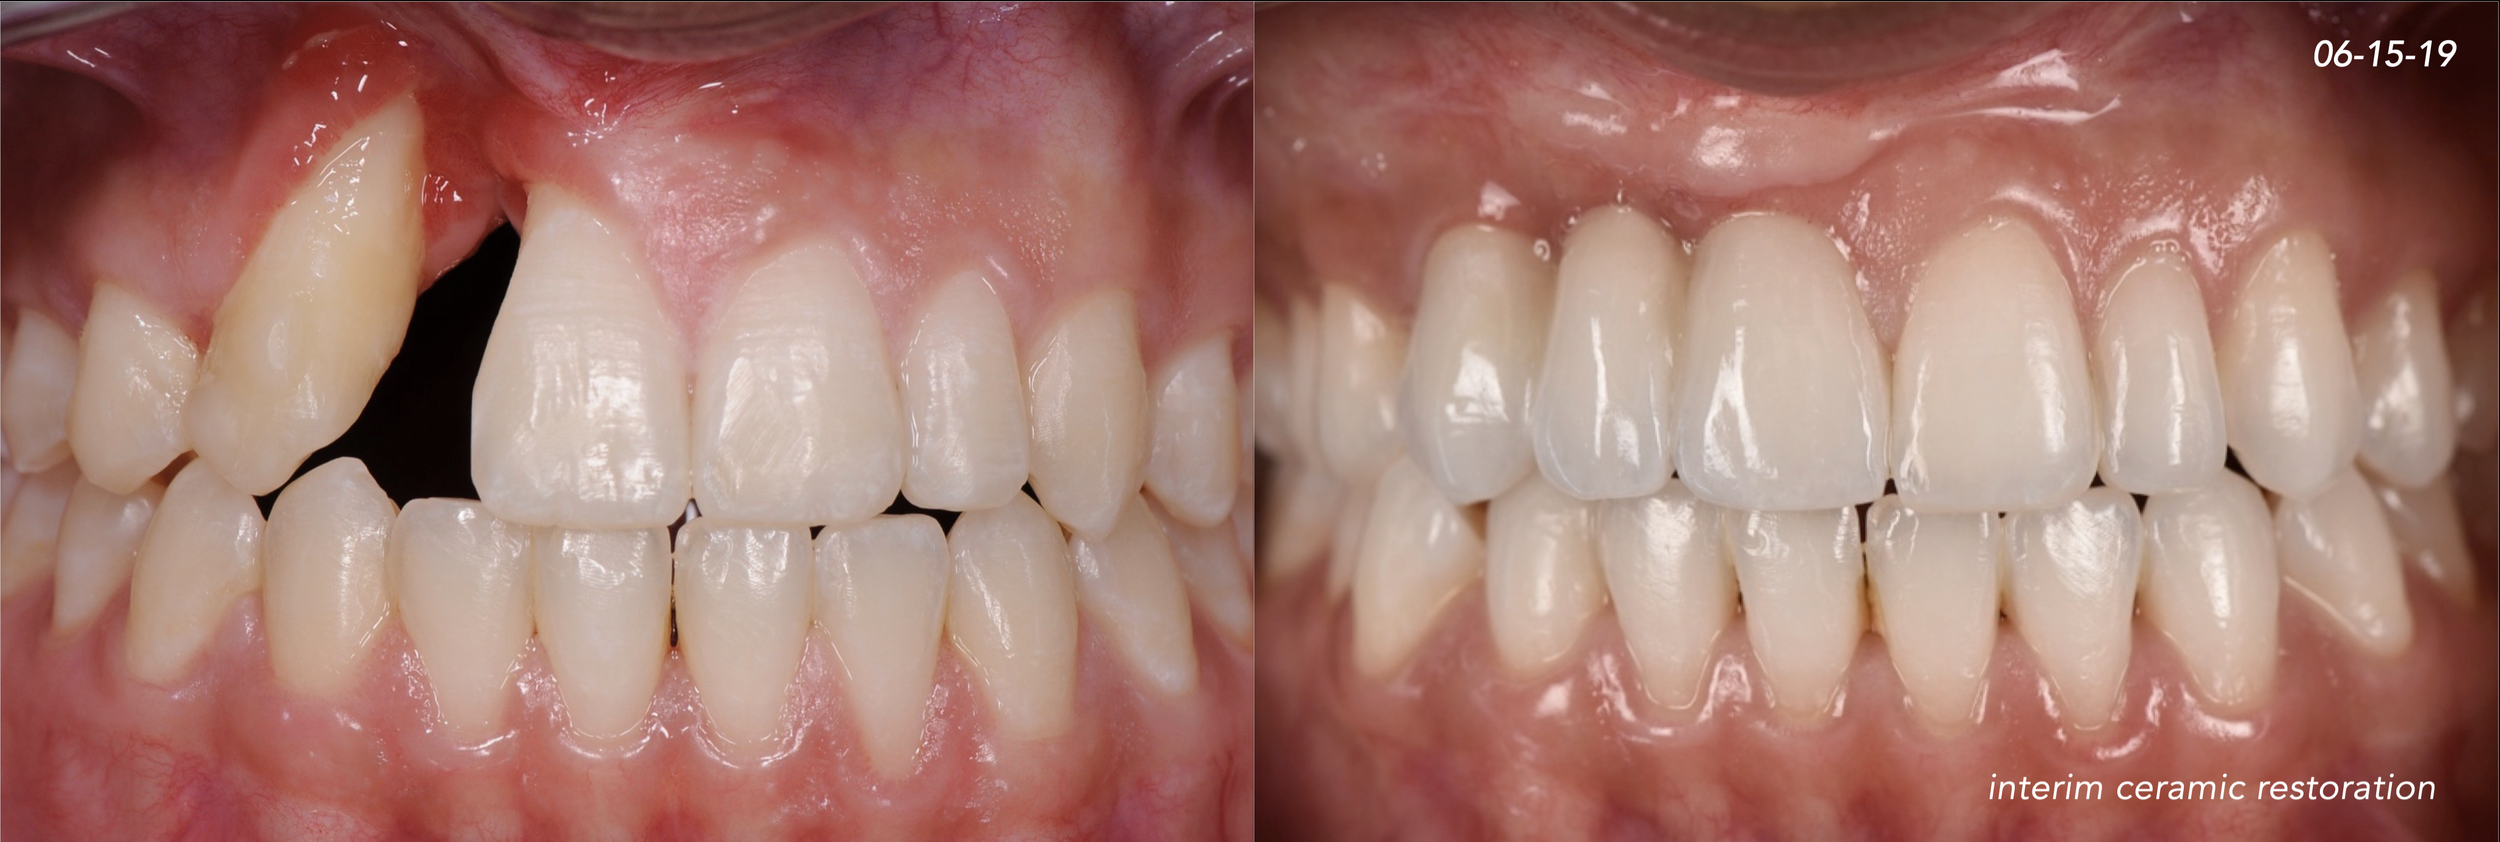

CASE 1. COMPLEX IATROGENIC DEFECT